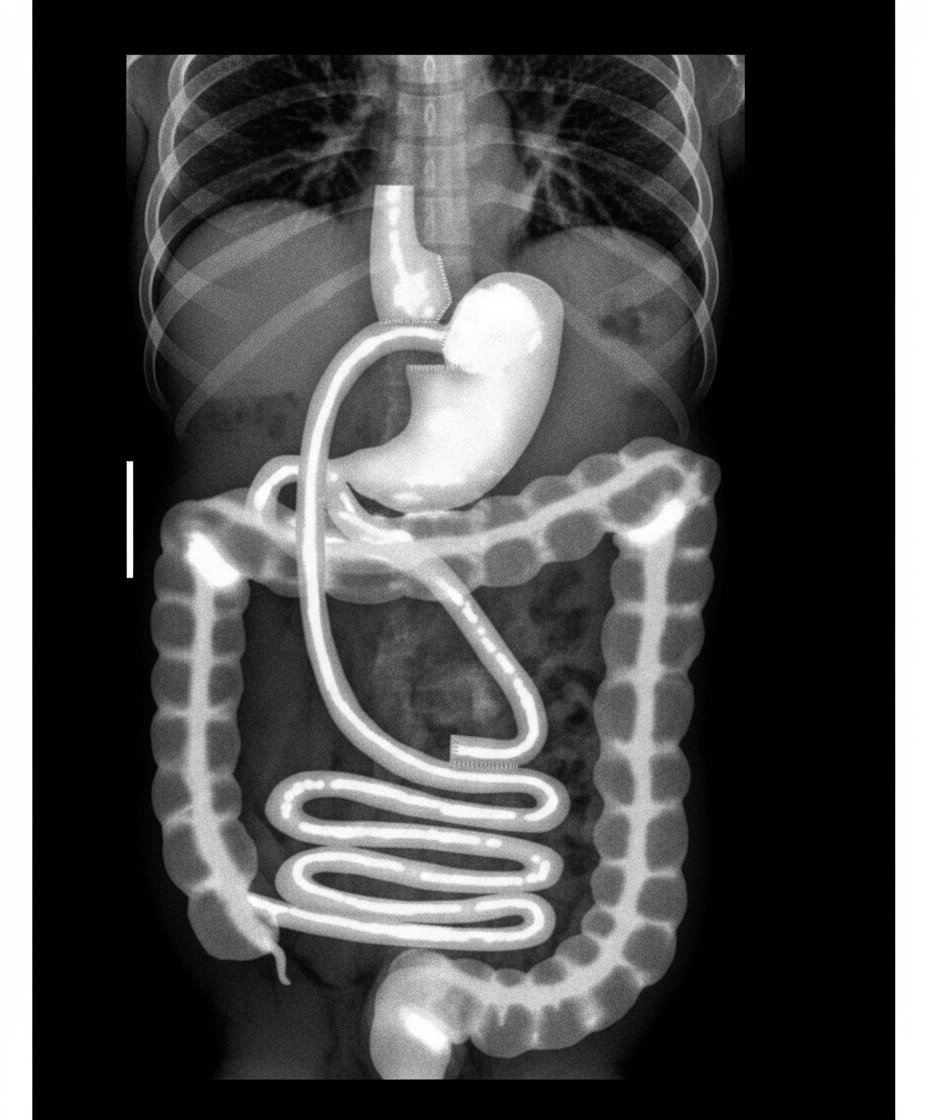

What procedure was most recently performed on this patient?

Explanation: ***Roux-en-Y gastric bypass*** - The imaging shows a **small gastric pouch** with **gastrojejunostomy** and **Roux limb** on upper GI contrast study, which are characteristic anatomical features created during this bariatric procedure. - This procedure creates a distinctive **Y-shaped configuration** where the jejunum is divided and rearranged to bypass most of the stomach and duodenum. *Mitral-valve repair* - This is a **cardiac procedure** performed on the mitral valve within the heart, not involving any abdominal structures. - Would require **echocardiography** or **cardiac catheterization** for evaluation, not upper GI contrast studies. *Pancreatectomy* - This procedure involves **surgical removal** of part or all of the pancreas, typically for **pancreatic cancer** or chronic pancreatitis. - Would show **absent pancreatic tissue** and possible **pancreaticojejunostomy** anastomosis, not the gastric pouch and Roux limb configuration seen here. *Thyroidectomy* - This is a **neck surgery** involving removal of the thyroid gland, completely unrelated to abdominal anatomy. - Post-operative imaging would focus on the **neck region** and would not show any gastric or intestinal changes.